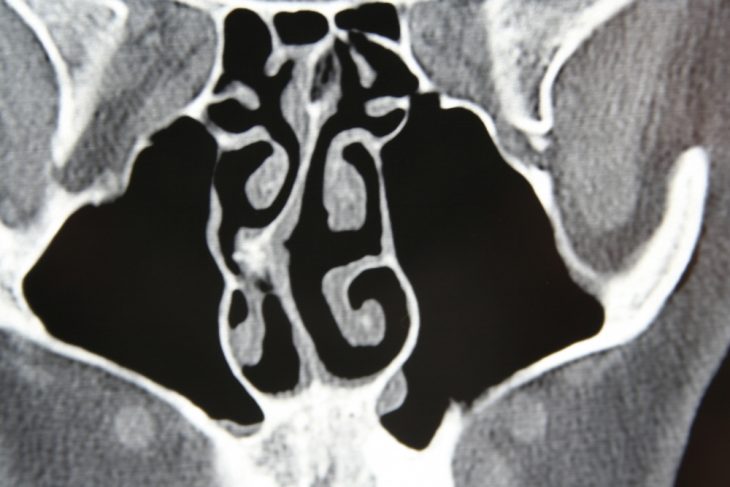

Носовая перегородка – это анатомическое образование, представляющее собой пластинку, которая разделяет полость носа на две половины. Передняя ее часть образована хрящевой тканью, а задняя – тонкой костью. Искривление перегородки носа – это довольно распространенное заболевание, которое встречается в любом возрасте и характеризуется целым комплексом симптомов.

Степень выраженности симптомов заболевания зависит от того, насколько сильно искривлена перегородка. Небольшое искривление носовой перегородки, не вызывающее никаких симптомов, встречается у многих людей. В таких случаях лечение обычно не требуется.

- Затруднение носового дыхания, вплоть до его полного отсутствия. При одностороннем искривлении нарушение воздухопроведения будет наблюдаться с одной стороны носа. Следует отметить, что у многих пациентов с выраженной деформацией носовой перегородки этот симптом может полностью отсутствовать.

- Частые воспалительные заболевания околоносовых пазух – синуситы (гайморит, этмоидит, фронтит), возникающие в результате нарушения оттока отделяемого из пазух по носовым ходам. Скопление секрета в полости придаточных пазух создает благоприятные условия для развития инфекции.